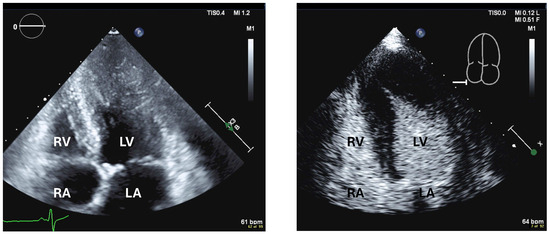

| Imaging method | Low-MI-contrast-specific imaging, alternatively intermediate-MI-contrast-specific imaging |

| Imaging planes | First try subcostal view, then standard views |

| Contrast application | Bolus injection |

| Typical findings | Usually isolated bubbles in the pericardial fluid Review frame by frame! |

| Alternative imaging | Cardiac computed tomography with contrast |